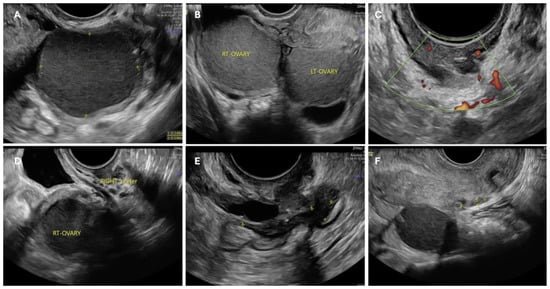

- Guerriero, S.; Condous, G.; van den Bosch, T.; Valentin, L.; Leone, F.P.G.; Van Schoubroeck, D.; Exacoustos, C.; Installé, A.J.F.; Martins, W.P.; Abrao, M.S.; et al. Systematic approach to sonographic evaluation of the pelvis in women with suspected endometriosis, including terms, definitions and measurements: A consensus opinion from the International Deep Endometriosis Analysis (IDEA) group. Ultrasound Obstet. Gynecol. Off. J. Int. Soc. Ultrasound Obstet. Gynecol. 2016, 48, 318–332. [Google Scholar] [CrossRef]